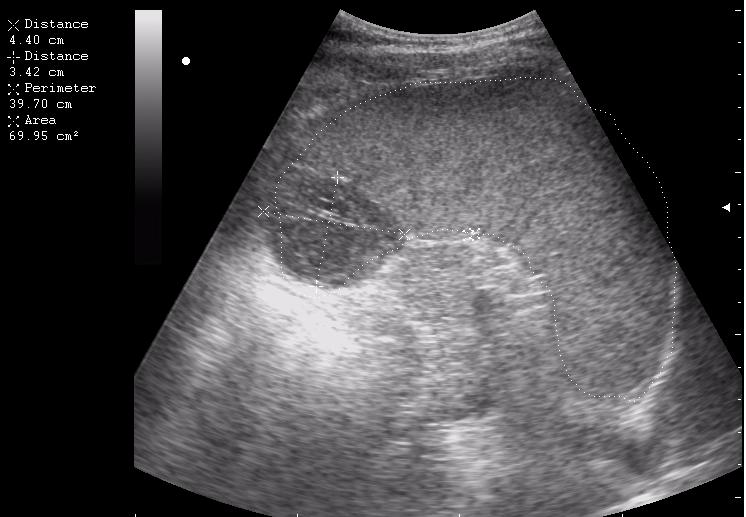

наезд большой черной Прады на маленькую (13кг) 5-летнюю девочку.

получает Медаксон, рабочая версия - изменение желчного пузыря вследствии травмы (шепотом - рекомендация хирургу сменить антибиотик)

сегодня был селезёночный день.